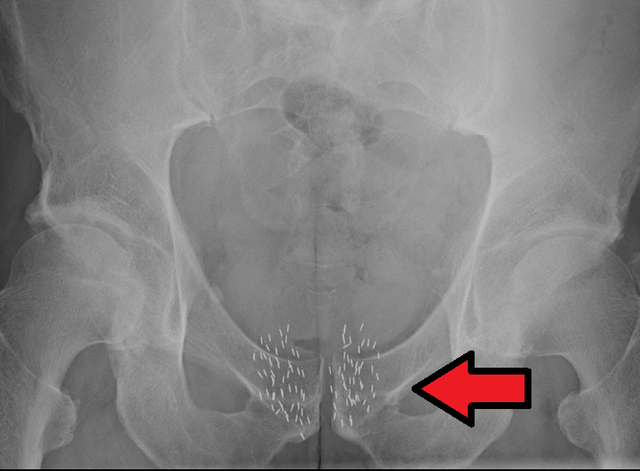

• Brachytherapy

Brachytherapy

-Brachytherapy used to treat prostate cancer was first pioneered by Benjamin Barringer.

-Used 4-6 inch radium needles through the perineum to the prostate.

-to help guide the needles they used their finger by going into the rectum to feel the prostate.